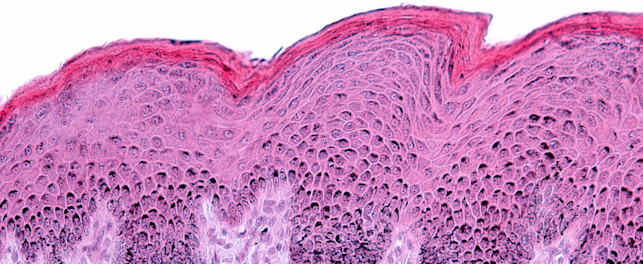

Humanity's quest for youthful, resilient skin stretches back thousands of years, from the natural oils and herbal remedies used by ancient civilizations to the evidence-based approaches of today. Modern science now recognizes skin longevity as more than just aesthetics. It encompasses the preservation of physiological integrity over time, supported by objective biomarkers and validated clinical endpoints.

Our new white paper examines the biological drivers of skin aging and details how advanced, non-invasive techniques are transforming clinical evaluation. By combining imaging, biomechanical assessment, biomarker analysis and hydration and barrier function measurements, researchers can now generate multi-dimensional data to scientifically substantiate product claims.